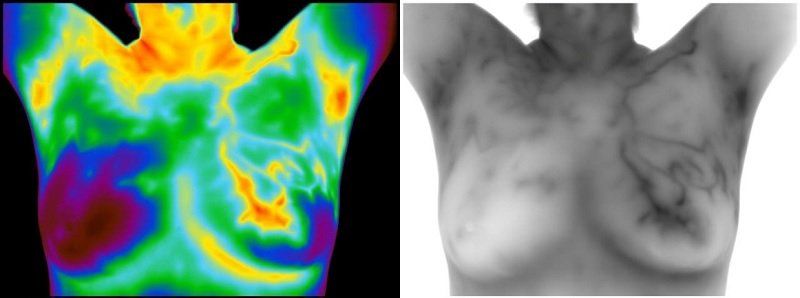

Thermography uses no radiation and no body contact, but instead the camera and software read the infra-red heat radiating from the surface of the body. It notes heat patterns and vascularity patterns. Abnormal heat and vascularity patterns detect a problem in process or starting.

Organizations like the International Academy of Clinical Thermology or the American Academy of Thermography will have research cited and accurate information. The IACT properly trains and certifies technicians and has a list of qualified providers. In choosing a thermography provider, always ask if the camera used will capture the images in “greyscale”. This is the top technology and will provide the higher resolution images where vascularity can best be studied. Always ask.